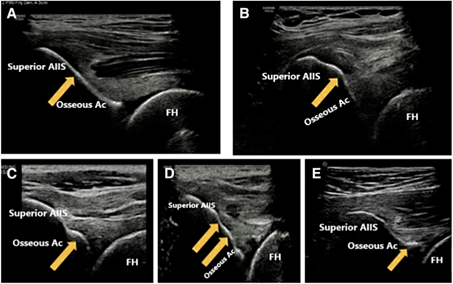

髂前下棘撞击(SSI)是FAI患者中常见的合并疾病,传统的诊断方式主要依赖于X线与CT检查。为了进一步改进诊断方法,我科对40名SSI患者进行了超声检查分析。研究发现,髂前下棘(AIIS)的骨形态Ⅲ型、前上关节囊和股直肌(dRF)腱直头内的不均匀性低回声与SSI的发生密切相关。特别是前上关节囊的异质性低回声,其在SSI的诊断中表现出较高的价值,灵敏度达到85.0%,特异度为58.1%,AUC值为0.681。此外,通过综合多个超声指标,我们构建的超声复合指标的AUC值更是达到了0.750,显示出良好的诊断效能。超声评估还发现,AIIS附近的骨形态异常和软组织损伤与SSI的发生存在密切联系。这一发现为我们提供了更多的诊断依据,有助于更准确地判断患者的病情。超声作为一种无创、便捷的检查方法,在SSI的诊断中具有重要的应用价值。它不仅可以作为一种可行的SSI预测方法,而且与CT相结合可以进一步提高SSI的诊断价值。

Sun Y, Liu R, Tian Y, Fu Q, Zhao Y, Xu Y, Cui L. Ultrasound Assessment of Hip Subspine Bone Morphology Soft-tissue Correlates with Clinical Diagnosis of Impingement. Arthroscopy. 2023 Oct;39(10):2144-2153.

超声对于髂前下棘的定性评估